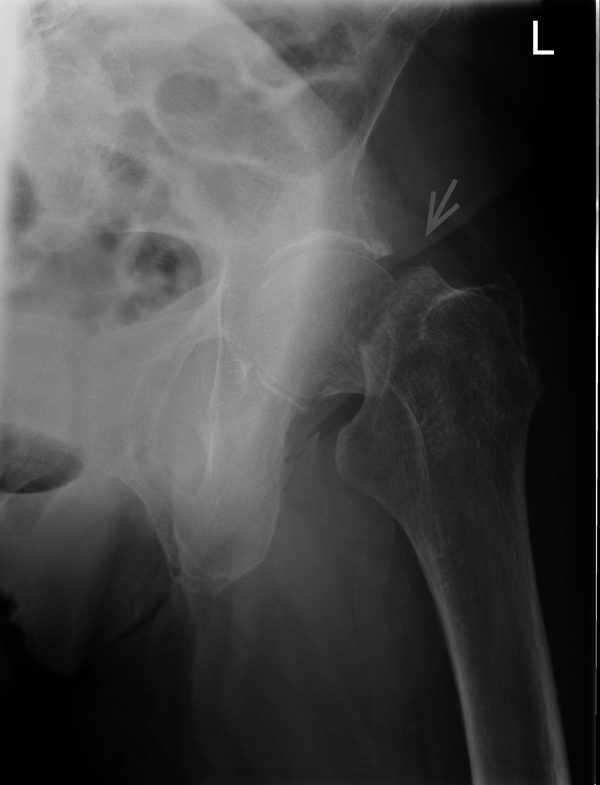

Решающее значение в установлении диагноза перелома шейки бедра имеет рентгенография тазобедренного сустава. У пожилых пациентов приведенные выше симптомы могут проявляться нечетко, а такие заболевания как инсульт или невропатия, вообще, не позволят поставить правильный диагноз без рентгена. Где сделать рентген? Перелом шейки бедра всегда сопровождается сильной болью, поэтому любые лишние движения оборачиваются новыми мучениями, а сопутствующие заболевания внутренних органов усугубляют ситуацию! Решение есть - воспользоваться уникальной услугой – цифровой рентген на дому. К вам приедет врач рентгенолог-травматолог, который выполнит весь комплекс лечебно-диагностических мероприятий и подробно расскажет, что делать дальше.

Получение качественных рентгеновских снимков на дому предъявляет серьёзные требования к рентгеновской аппаратуре. Далеко не каждый переносной рентгенаппарат позволяет получать снимки необходимого качества, чтобы достоверно поставить диагноз. Используемый нами рентгенаппарат АРА 110/160 в комплексе с компьютерным радиографом позволяет получать цифровые рентгеновские снимки высокого качества у пациентов различной комплекции и является уникальной услугой в Санкт-Петербурге, предоставляемой на дому.